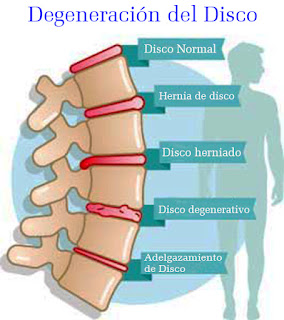

La escoliosis secundaria puede ser causada por una enfermedad neuromuscular o ósea, o por una deformación en el nacimiento. Además, la escoliosis degenerativa o "de novo", es la escoliosis que se encuentra más adelante en la vida. Es causada por un deterioro de los discos intervertebrales y vertebrales vinculados a la edad. La escoliosis degenerativa es más común, ya que la duración de la vida aumenta constantemente.